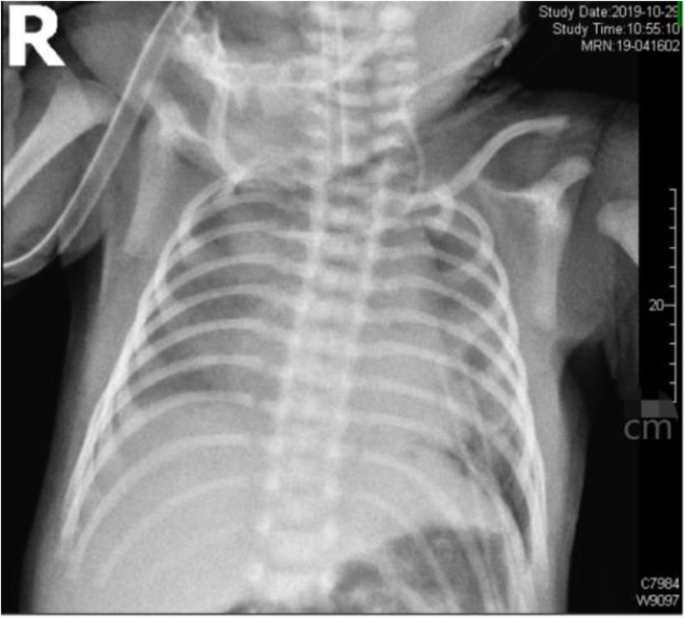

No patients younger than this case were found in the existing literature for thoracoscopic lobectomy. The respiratory circulation of this child was difficult to maintain, so surgical treatment was selected. Thoracoscopy was performed at 4 days after birth. The patient was positioned on the right side with the left arm elevated. Two 5-mm trocars and one 3-mm trocar were used. One 5-mm trocar was positioned in the 8th intercostal space of the midaxillary line as the observation trocar, another 5-mm trocar was positioned in the 7th intercostal region of the posterior axillary line, and the 3-mm trocar was positioned in the 5th intercostal region of the anterior axillary line after artificial pneumothorax. The left thoracic cavity was filled with a giant CPAM (Fig. 5), and ultrasonic scalpel was used to open the cyst to make it smaller in order to expose the surgical field. The lower left lung was filled with several cystic structures. Hem-O-lock ligating clips were used to ligate the vessels. Clipping and division of the vessels and fissure followed by complete excision were performed, and the specimen was extracted through the 5-mm port site in the midaxillary line after spreading. The operation lasted 170 min. Histology confirmed the diagnosis of a CPAM. The postoperative course was uneventful. X-ray showed that the left lung recovered satisfactorily (Fig. 6). The child was extubated 6 days after surgery and discharged from the hospital 16 days after surgery. After surgery, the patient’s respiratory function and circulatory function recovered well. At 6 months post surgery, the child had no respiratory discomfort and performed normal activities, and no obvious abnormality was found upon reexamination of the chest radiograph.

The child in this case had an incomplete fissure, and after cutting off the inferior pulmonary vein, we found it difficult to expose the inferior pulmonary artery, and the pulmonary fissure appeared to bleed easily. Therefore, we chose to cut it from the periphery of the pulmonary fissure with an ultrasonic scalpel, dissecting it to the place near the inferior pulmonary artery, and then ligate the lower pulmonary artery and the lower pulmonary bronchus with No. 0 silk suture. After ligation, the lower lung tissue was removed; thus, there was no bleeding or air leakage in the section. A review of the X-ray results demonstrated no residual cysts.